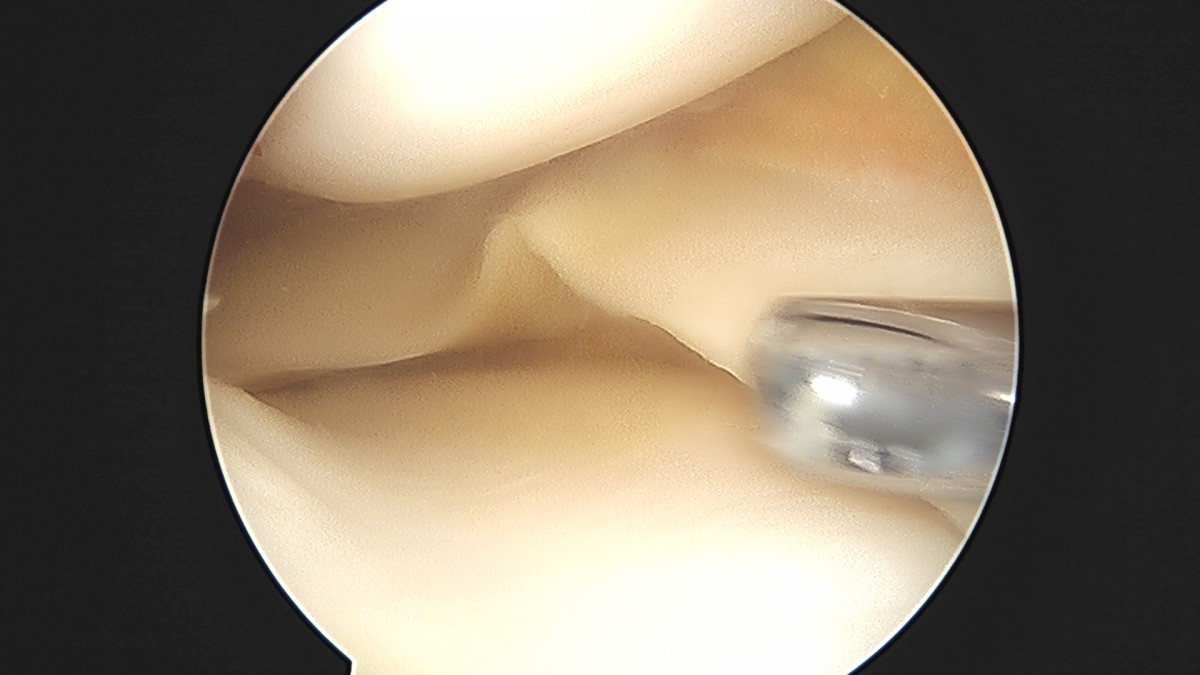

이재상원장님 전방십자인대 재건술 및 반월상 연골판 봉합술 윤두O 환자

작성자 최고관리자 댓글 0건 조회 704회 작성일 25-09-16 16:22